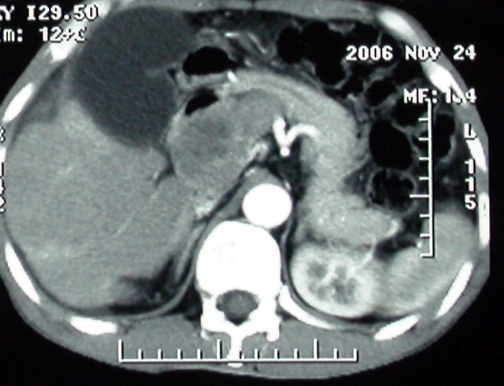

平扫

增强ct所见【动脉增强期】